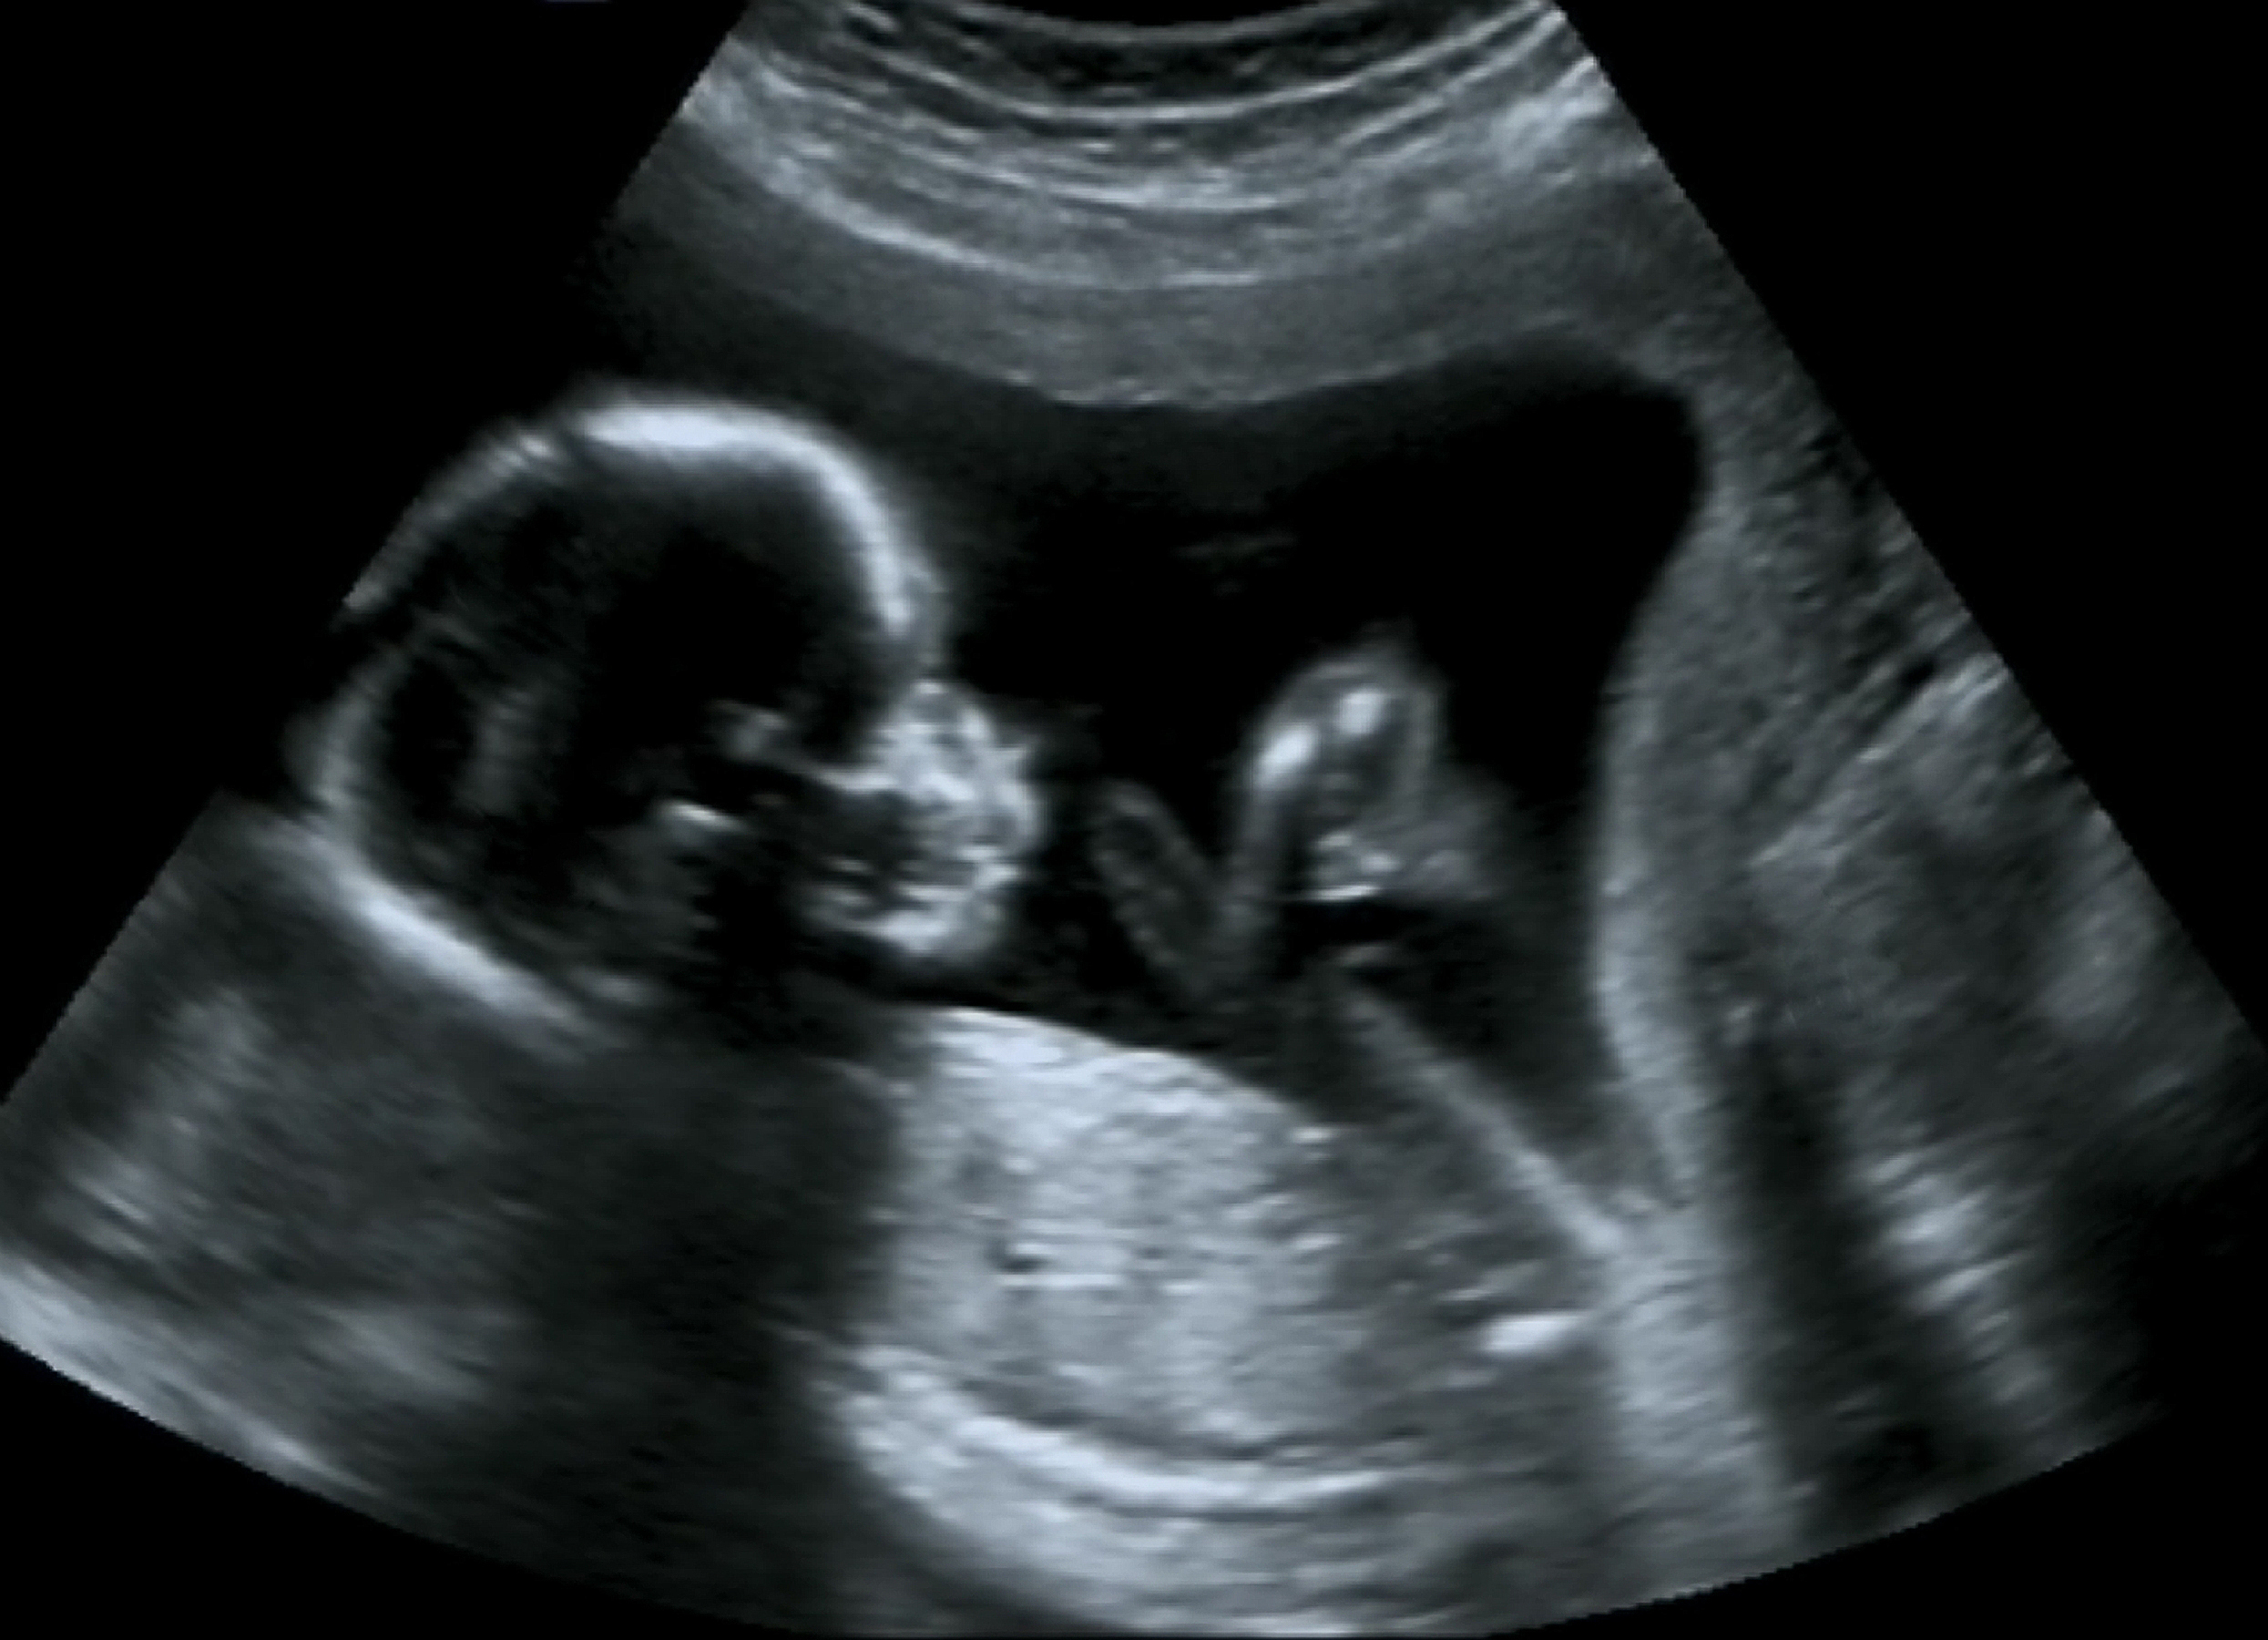

[To read the full story go to DeseretNews.com](<http://www.ksl.com/ad_logger/ad_logger.php?location=http://www.deseretnews.com/article/865585688/The-disputed-science-of-fetal-pain.html&s_cid=ksl-partner&sponsor=Abortion policy and disputed science: How soon do fetuses feel pain?>).